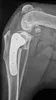

Using modern technology and ongoing training we strive to be leaders in veterinary care. We take referrals for our surgical and medical services. We have expertise in endoscopy, lap speys, orthopaedics, advanced soft -tissue surgery, exotics, acupuncture and more.